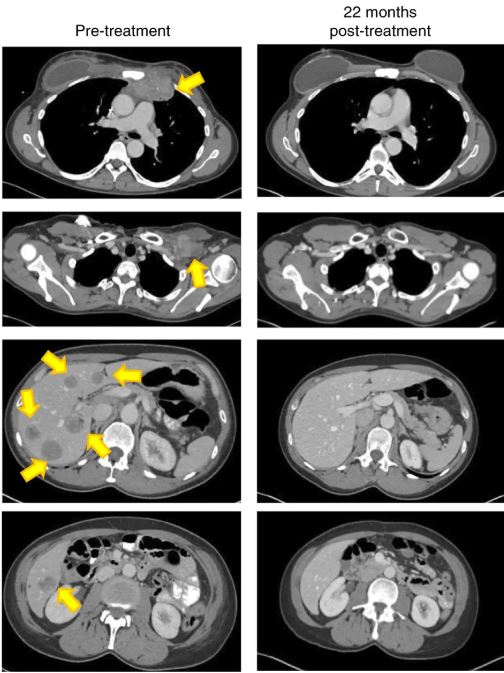

Два года назад врачи сказали Джуди Перкинс из Флориды, что ей осталось жить три месяца. Сегодня в ее теле нет и следа раковой опухоли.

У Джуди был рак груди на терминальной стадии — он быстро распространялся и не подлежал общепринятому лечению.

В ее печени были опухоли размером с теннисный мяч, метастазы распространились по всему телу.

О своем опыте экспериментального лечения она рассказала журналистам: «Примерно через неделю после начала терапии я начала что-то чувствовать. В моей груди была опухоль, и я чувствовала, как она сжимается. Еще в одну-две недели она совсем исчезла».

Она вспоминает также первую томограмму после процедуры — все медперсонал «был очень взволнован и даже подпрыгивал».

Тогда же ей сообщили, что она полностью здорова.